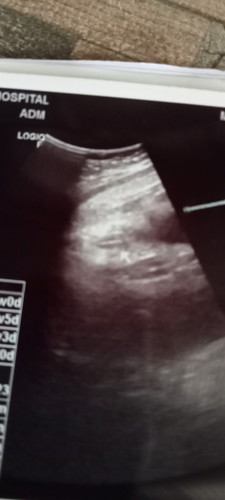

ทีมลูกสาว34วีค 22กุมภาพันธ์

วินาทีจะคุณหมอบอกลูกสาวตื้นตันใจแบบบอกไม่ถูกเลยคะ😁☺️☺️💕💕 ทีมลูกสาวค่ะ 22 กุมภาพันธ์ ทั้งดีใจทั้งตื่นเต้น💗💗💗